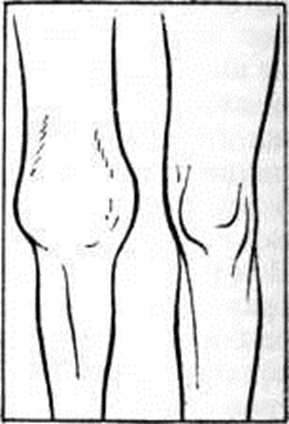

В крови при острых Гонит выявляется лейкоцитоз (иногда до 25 000), значительное ускорение РОЭ (до 70 миллиметров/час), резкие сдвиги биохимический показателей. В ряде случаев острое течение Гонит переходит в хроническое. При под острых Гонит все описанные симптомы выражены в меньшей степени. При хронический Гонит не обязательно определяются все симптомы воспаления коленного сустава. Боль возникает главным образом при движении в суставе. Характерны стойкие изменения формы сустава (рисунок 2) в результате органического поражения суставной капсулы, мышечной атрофии, развития артромиогенной контрактуры. Хронический Гонит моноартикулярного типа может протекать без повышения температуры тела, ускорения РОЭ. В связи с разнообразием этиологического факторов, а также анатомо-функциональными особенностями коленного сустава, характеризующегося большой площадью сочленяющихся суставных поверхностей, обширной суставной капсулой, течение Гонит отличается большой вариабельностью. |

Рис. 2. | ||